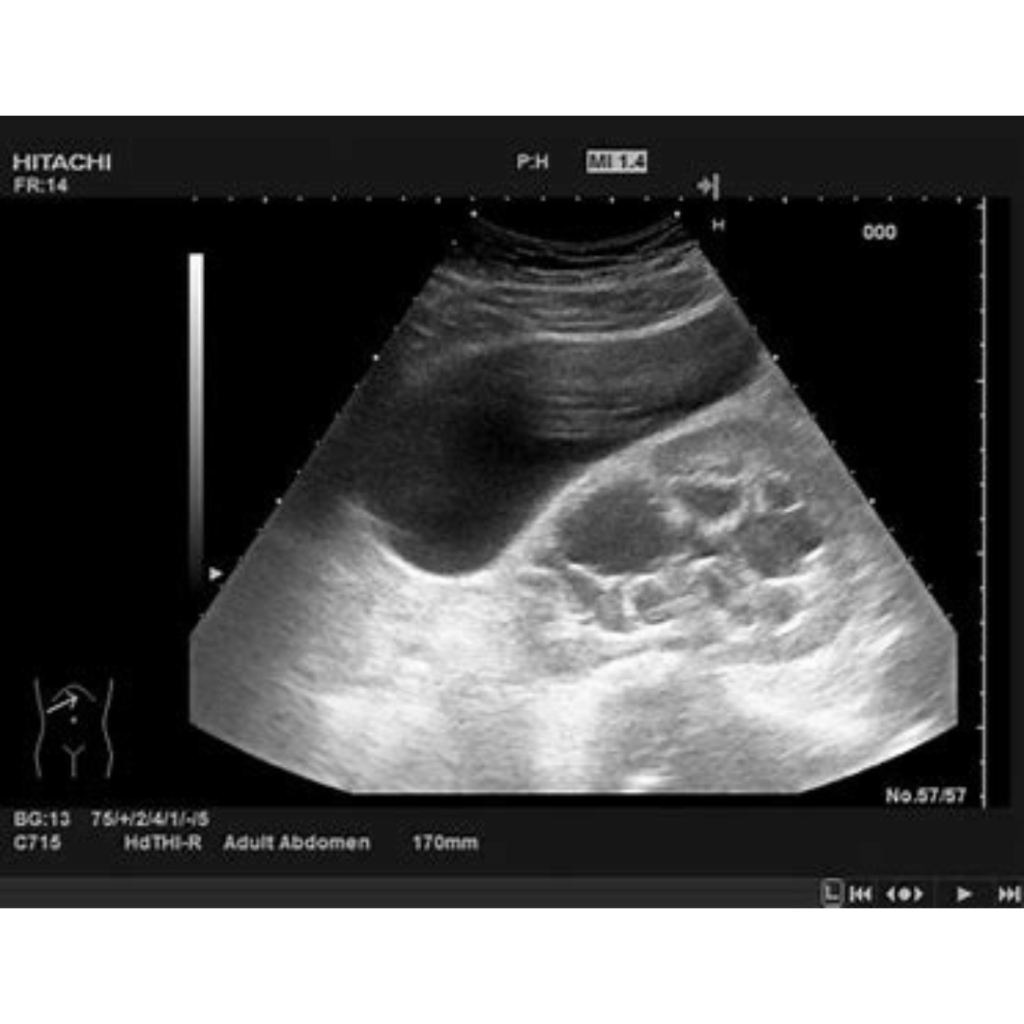

A pelvic ultrasound is a medical test that uses sound waves to create images of the organs in the pelvic area, such as the uterus and ovaries in women, and the bladder and prostate in men. This procedure helps detect cysts, fibroids, tumors, kidney stones, and other abnormalities. Doctors recommend it to investigate symptoms like pelvic pain, abnormal bleeding, or fertility issues. The pelvic ultrasound is a safe, non-invasive tool that provides valuable information for diagnosing and treating various conditions.